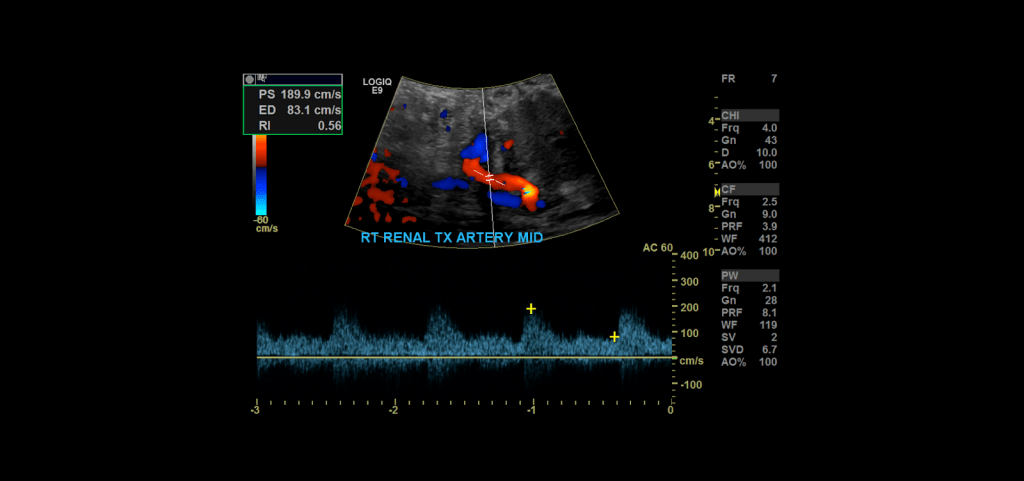

Proceed to doppler the transplant main renal artery and vein. Given the tortuosity sometimes seen in the donor arteries, measuring velocities with angle correction can be tricky. My rule of thumb is that if the artery is perpendicular to the transducer face I don’t use angle correction. If it is parallel to the transducer face I do use angle correction.

Measure the peak systolic and end diastolic velocity. Resistive Index is normally between 0.50 and 0.70. The waveform should be a low resistance waveform with forward flow throughout the cardiac cycle. Take Doppler samples at the anastomosis/proximal section (pay close attention here look for aliasing to detect anastomotic stenosis), the mid and distal portions as well. If there’s any aliasing along the vessel take spectral Doppler samples there too.